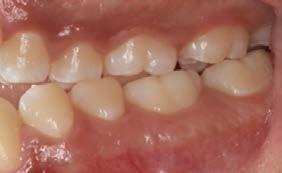

Caso clínico: paciente femenino de 19 años, patrón dolicofacial, perfil convexo, clase II esqueletal debido a una retrusión mandibular, mordida abierta anterior esqueletal, clase II molar, clase canina no establecida por mordida abierta, apiñamiento severo superior e inferior y deglución atípica.

Resultados: obtención de una clase canina I y clase molar II funcional, se corrigieron las sobremordidas horizontal y vertical, y se logró la coincidencia de líneas medias facial y dental. El manejo de la mordida abierta anterior se llevó a cabo por medio de la corrección del hábito de deglución atípica con la ayuda de spikes de resina, elásticos intermaxilares y arcos utility, y se obtuvieron buenos resultados estéticos, dentales y funcionales.